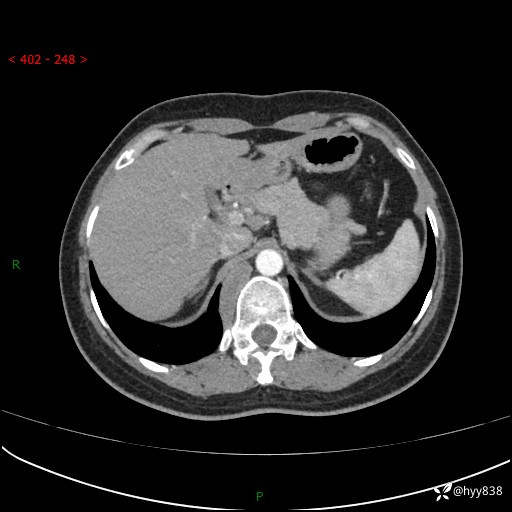

简要病史:患者于1天前因体检发现右旁肾占位,无肉眼血尿,无畏寒发热,无咳嗽咳痰,无腰腹部疼痛不适,无尿频尿急症状,起病来,患者未行特殊治疗,为求进一步诊治,门诊以"右侧腹膜后肿物"收治入院。 发病来患者精神、饮食、睡眠良好,小便如上,大便正常,体重无明显变化。

辅助检查:CT

临床诊断:腹膜后肿物

上腹部CT增强(动脉期+实质期)(外院平扫)